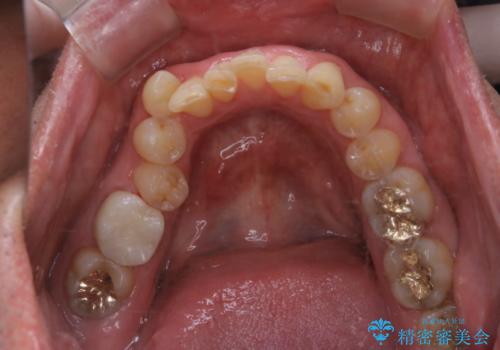

- 被せ物の治療が終了したためメンテナンスに入る前に全体的なチェック・クリーニングを行いました。

歯科衛生士による専門的なクリーニングPMTC(保険外治療)60分コースを行いました。

専門的な機械・材料を使用して徹底的に汚れを取り除きました。

染め出しをして、磨き残しの確認・ブラッシング指導も行いました。